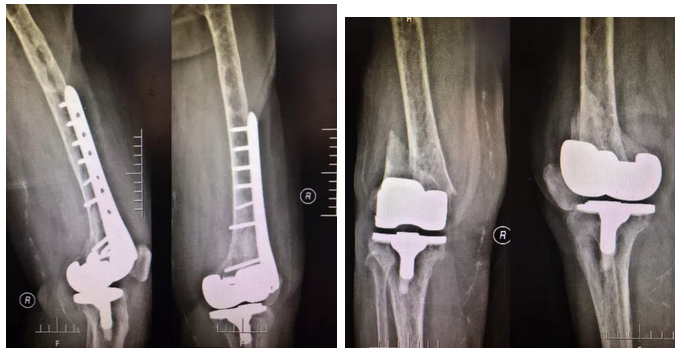

71岁的王大妈因右股骨远端假体周围骨折于10月26日来骨伤二科住院治疗,鉴于王大妈多病缠身,身体情况较差,纪忠义主任带领科室医护人员多次探讨病情,组织内科医生会诊,制定了缜密的手术方案,并于10月31日,成功为其实施了骨折切开复位锁定钢板内固定术。

原来王大妈是骨伤二科的“自己人”,10年前就与这里结下了不解之缘。2009年因右膝骨性关节炎在骨伤二科住院治疗,为其成功实施了右侧人工膝关节置换术;2015年因左侧肱骨干骨折先后两次住院手术治疗。虽然老人有过其他医院的住院经历,但老人和家属始终感觉在青岛西海岸新区中医医院住院治疗有一种格外温暖和踏实的感觉,对骨伤二科全体医护也有一种莫名的亲切和信任,这次老人受伤后,他们毫不犹豫的再次选择来这里住院治疗。